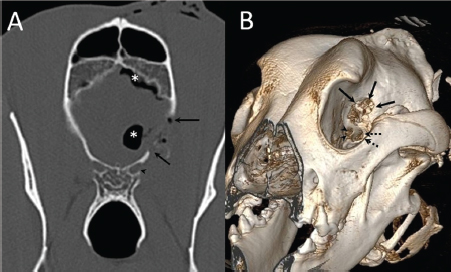

A 3-year-old female Great Dane was referred for acute onset behavioral changes (aggression and disorientation) of 2 weeks duration, and seizures from 24 hours prior to presentation. Physical examination revealed no abnormalities in body temperature, body condition score, heart rate, pulse quality, or cardiopulmonary auscultation. All lymph nodes were considered of normal size and no pain was elicited upon manipulation of the orbital, aural, or cranial musculature. Neither was there any history of dermatological or traumatic lesions in the eye, ear, or mouth. The neurological examination revealed the patient to be obtunded with decreased postural reactions and menace response worse in the left side. Neuroanatomic lesion localization was considered focal in the right prosencephalon with a possible increase in intracranial pressure. Hematological and serum biochemical analysis showed no abnormalities. Magnetic resonance imaging was performed using a low-field magnet (Airis Mate; Hitachi, Tokio, Japan). The study revealed a left-sided single frontal intra-axial lesion affecting gray and white matter adjacent to the internal capsule at the level of the optic canal (Fig. 1). The lesion presented signal homogeneity characterized by hyperintensity on T2W and FLAIR sequences and hypointensity in T1W sequences with peripheral enhancement after intravenous contrast administration (Fig. 1A and 1B). The lesion had a round shape with the greatest diameter of 2.84 cm. This enhancement was also recognized in the surrounding meninges following the brain surface following sulci. A small linear tract observed was directed dorsally from the lesion through the corona radiata (Fig. 1B). The lesion was associated with extensive perilesional vasogenic edema that worsened the mass effect characterized by a midline shift. The orbital and medial pterygoid muscles also showed an intense enhancement (Fig. 2). The wing of the presphenoid bone was thinner than the contralateral bone (Fig. 1B). A CT scan (Astelion 16, Toshiba, Tokio, Japan) was performed after MRI that allowed the identification of osteolysis in the presphenoid bone immediately dorsal to the orbital fissure (Fig. 1C). CT scan also revealed a hypoattenuating intra-axial lesion located in the left frontoparietal lobe together with diffuse hypoattenuation of tissues adjacent to the left optic nerve and the left pterygoid muscle. Finally, CSF analysis showed no abnormalities. On the basis of advanced radiological findings, the main differential diagnosis was an intracranial abscess due to the extension of the extracranial septic process through presphenoid bone. Because of rapid neurologic deterioration and suspected increased intracranial pressure, surgical excision was planned. A modified left rostrotentorial craniectomy was performed. Temporalis muscle and fascia were retracted, extending the incision cranially through the temporal line. Once the frontal and presphenoid bones were exposed an area of osteolysis was observed in the wing of the presphenoid bone immediately dorsal to the orbital fissure. The craniectomy (approximately 3 cm diameter) was centered on the osseous defect. A mucopurulent discharge presented immediately after the incision of the dura mater. A sample was collected for its microbiological study. The surgical site was flushed with sterile saline revealing the tip of a grass awn which was extracted from the brain parenchyma together with a small amount of purulent fluid (Fig. 3). After extensive flushing, the meninges were left open to allow drainage and the incision was closed as per routinely. Postoperative CT showed the correct location of the craniectomy and resolution of the abscess which was substituted by gaseous content but remained inside and on the dorsal surface of the frontal lobe (Fig. 4). Immediate postoperative therapy consisted of amoxicillin + clavulanic acid (Synulox 500, Zoetis Spain SL) 22 mg/kg PO, q8h; marbofloxacin (Marbocyl P80, Vetoquinol SA) 5 mg/kg PO, q24h; metronidazole (Flagyl 250, Sanofi-aventis SA) 15 mg/kg PO, q12h; prednisone (Prednisona Kern Pharma 30mg, Kern Pharma) 0.5 mg/kg PO, q12h; tramadol (Tramadol retard Combix 100 mg, Laboratorios Combix S.L.U) 2 mg/kg PO, q8h; famotidine (Famotidina Normon 40 mg; Laboratorios Normon SA) 0.7 mg/kg PO, q24h; and phenobarbital (Phenoleptil 100 mg, Le Vet BV) 2.5 mg/kg PO, q12h. Cultured samples were positive for Pseudomonas aeruginosa sensitive to ciprofloxacin, imipenem, and amikacin among other antibiotics. Based on these results, antibiotic therapy was changed to ciprofloxacin (Ciprofloxacino 500, Laboratorios Normon SA) 10 mg/kg PO, q12h and metronidazole 15 mg/kg PO, q12h for 2 months. Prednisone, tramadol, and famotidine were withdrawn and phenobarbital was maintained at 2.5 mg/kg q12h. Six-month post-operative revision magnetic resonance revealed no signs suggesting the existence of an inflammatory process (Fig. 5). In the area where the abscess had been located, a fluid-filled cavity suggesting being CSF was observed. One year follow-up revealed the patient had seizures every 3 months with neurological examination remaining normal. The patient died 2 years later of unrelated causes.

Fig. 2. (A) Transverse and (B) dorsal post-contrast T1-weighted images revealing enhancement of orbital musculature and medial pterygoid muscle (arrows).